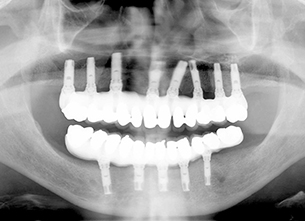

症例1 : 上下顎無菌顎症例

69歳、男性。

• 上顎は両側サイナスリフトと同時に即時荷重を行った。

• 下顎は抜歯即時埋入即時荷重を行った。

• 最終補綴物は、チタンのP.I.B.とM.B.のコンビネーションで修復した。

• 本症例の要旨は第39回日本口腔インプラント学会(大阪)にて症例報告した。